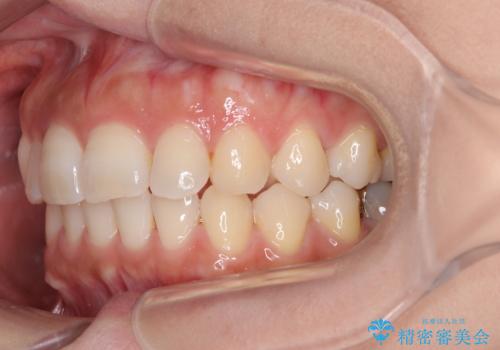

目立つ八重歯を改善 ワイヤー装置での抜歯矯正

- 目立つ八重歯を気にして来院された患者様です。

上顎小臼歯を抜歯するかどうか悩みましたが、八重歯の後方に失活歯があること、治療前に上顎正中が概ね人中に合っていることから、右上第二小臼歯を抜歯することとしました。

片側での抜歯であると、正中が抜歯した方向にずれていくため、左上の奥歯を遠心移動させる目的でアンカースクリューと補助装置を併用した上で、ワイヤー装置にて矯正治療を行うこととしました。

上顎の正中位置をほぼ保った状態で、綺麗に仕上げることができました。